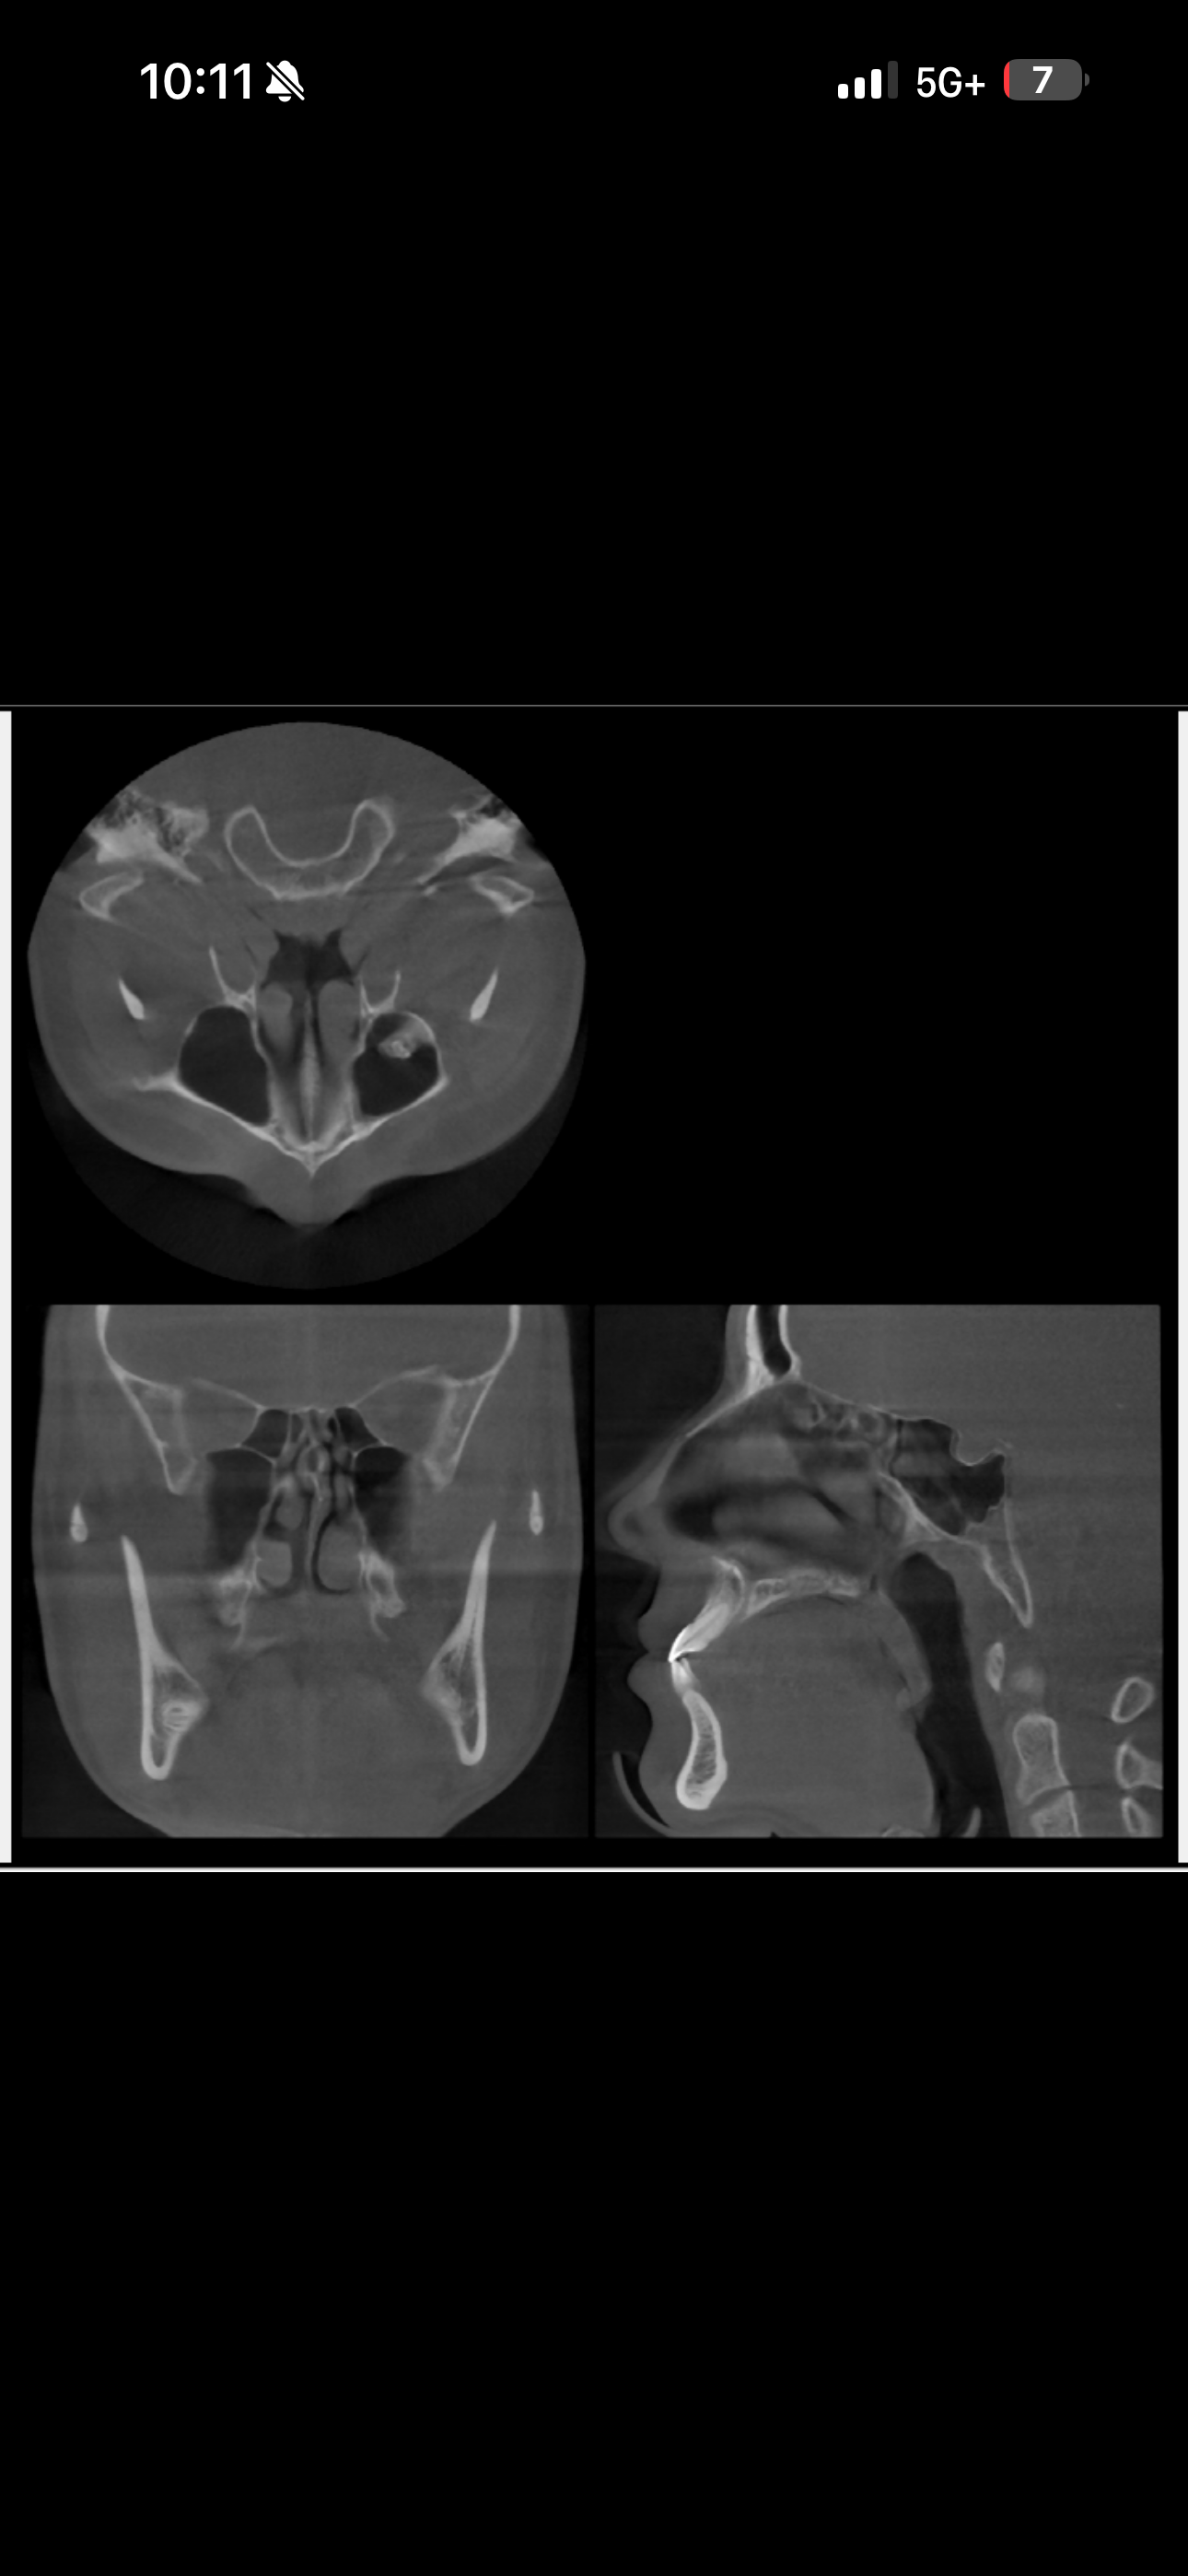

This is a CBT Scan I did a couple years back. Based on this results do I have proper tongue posture? I’m definitely looking into getting my septum deviation corrected.